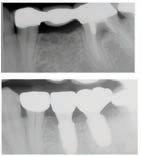

๊ฑด๊ฐํ ๋ฏธ์, ํดํผ์ค๋ง์ผ ์น๊ณผ์์

์์ํ์ธ์.

์ต์ ์ฅ๋น์ ์น์ ํ ์ง๋ฃ, ์ํ๋ํธ๊น์ง ๋ฏฟ๊ณ ๋งก๊ธฐ์ธ์!

๊ฐ์กฑ ๋ชจ๋์ ๋ฐ์ ๋ฏธ์๋ฅผ ์ง์ผ์ฃผ๋ ํดํผ

์ค๋ง์ผ ์น๊ณผ์์๋ ๊ฑด๊ฐ๋ณดํ๊ณผ ๋ฉ๋์ผ์ด,

๋ค์ํ PPO ๋ณดํ์ ์ทจ๊ธํ๋ฉฐ, ์์ฝ๋ถํฐ

์ง๋ฃ๊น์ง ๋ชจ๋ ๊ณผ์ ์์ ํ์์ ํธ์์

๋ง์กฑ์ ์ต์ฐ์ ์ผ๋ก ํ๋ค.

ํนํ ํดํผ์ค๋ง์ผ ์น๊ณผ๋ ์ํ๋ํธ ์น๋ฃ

์ ๊ฐํ ์์ ๊ฐ์ ๊ฐ์ง๊ณ ์๋๋ฐ, ์์์

์น์ ๋ ์ฌ์ฉํ๋ ํ, ์ฆ ์น์์ ํฑ ๊ทผ์ก

์ ์ฌ์ฉํ์ฌ ์์์ ์๊ฒ ๋ถ์๋ ๋ฅ๋ ฅ๊ณผ

์ฌ๋ฏธ์ฑ์ ๋์์ ๋ง์กฑ์ํค๋ ์ํ๋ํธ๋

์์ฐ ์น์์ ๊ฐ์ฅ ๊ฐ๊น์ด ๋์ฒด ์น๋ฃ๋ก, ํ

๋์ ๋นํด ๋ ๋จ๋จํ๊ณ ์ค๋ ์ฌ์ฉํ ์ ์

์ธ์ ์น์๋ฅผ ๊น์ ํ์๊ฐ ์์ด ๊ตฌ๊ฐ ๊ฑด๊ฐ์ ์ ์งํ๋ ๋ฐ๋ ๋์์ด ๋๋ค. ํดํผ์ค๋ง์ผ ์น๊ณผ๋ ๋ณต์กํ ๊ตฌ๊ฐ์ธ๊ณผ ์์ ๊ณผ ์ง๋จ์ ์ํด ์น๊ณผ์ ์ฉ 3D CT ์ค์บ๋๋ฅผ ๊ฐ์ถ๊ณ ์์ผ๋ฉฐ, ์ด๋ฅผ ํตํด ์ ํํ๊ณ ์์ ํ ์ํ๋

ํธ ์์ ์ด ๊ฐ๋ฅํ๋ค. ํฑ๋ผ ์ํ, ์ ๊ฒฝ ์์น, ๋ผ์ ๋ฐ๋๊น์ง ์ ๋ฐํ๊ฒ ๋ถ

์ํ์ฌ ํ์ ๊ฐ๊ฐ์ธ์๊ฒ ์ต์ ํ๋ ์น๋ฃ ๊ณํ์ ์๋ฆฝํด๋๋ฆฐ๋ค.

๋ฟ๋ง ์๋๋ผ, ์ฌ๋ฏธ๋ณด์ฒ ๊ณผ ๋ฏธ์ฉ์น๋ฃ, ์ผ๋ฐ์น๊ณผ, ์์์น๊ณผ, ๊ตฌ๊ฐ์ธ๊ณผ, ์ ๊ฒฝ

์น๊ณผ ๋ฑ ๋ค์ํ ๋ถ์ผ์ ์ ๋ฌธ ์๋ฃ์ง์ด ํจ๊ปํด ํ ํ ์น๊ณผ ์ง๋ฃ๋ฅผ ์์คํฑ ์ผ๋ก ์ ๊ณตํ๊ณ ์๋ค.

ํดํผ์ค๋ง์ผ ์น๊ณผ์์๋ ์ ํธ๋(Aetna), ์ค์ฌ(Anthem), ํด๋ ๋ฒ์ผ์ด (Clever Care), ์์คํฐ๋ฐ(Astiva), ํด๋จธ๋(Humana), ๋ฆฌ๋ฒํฐ(Liberty), ์ ๋ ์ดํฐ๋ํฌ์ค์ผ์ด(United Healthcare) ๋ฑ. ๋ค์ํ ๋ณดํ์ ์ทจ๊ธํ๊ณ ์๊ณ , ๋ฉ๋์นผ/๋ฉ๋์ผ์ด PPO ๋ณดํ ํ์ํ๋ค.

์ข์ ์ฌ๋ฃ์ ๊ณ ํ์ง ์ง๋ฃ, ์ต์ ๊ธฐ์ , ๊ทธ๋ฆฌ๊ณ ํ์๋ฅผ ์๊ฐํ๋ ์ง์ฌ์ด ์๋ ํดํผ์ค๋ง์ผ ์น๊ณผ์์ ์จ ๊ฐ์กฑ์ ๊ฑด๊ฐํ ๋ฏธ์๋ฅผ ๋์ฐพ์๋ณด์.

๋ฌธ์ ๋ฐ ์์ฝ: 818-775-1200